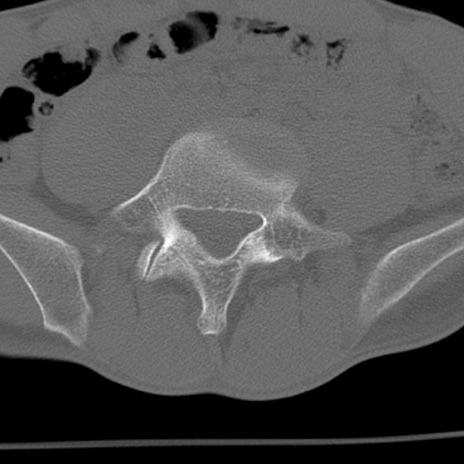

症例3 腰椎CT(横断像)

腰椎CT